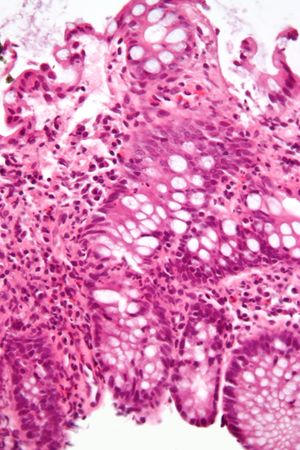

ميكروگراف يـُظهـِر cryptitis, a ارتباط مجهري لالتهاب القولون. H&E stain. | |